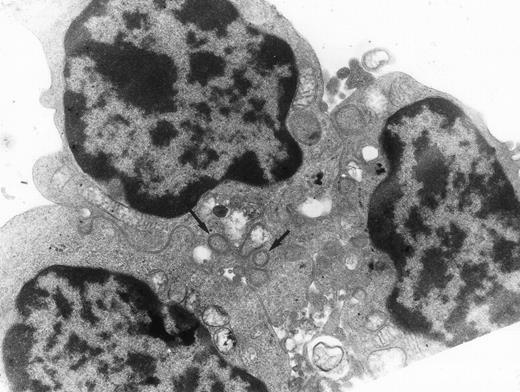

Electron microscopy.

Electron microscopy confirmed the diagnosis of erythroblastic synartesis in the 3 patients. Plasma membranes of adjacent erythroblasts were joined by closely interdigitating processes (Fig2). Cytochemical demonstration of the peroxidatic activity of hemoglobin (not shown) allowed identification of maturation stages of the erythroblasts, because its level of intensity relates to the hemoglobin content of each cell. This technique showed that erythroblasts of the same maturation stage, as well as those of different maturation stages, were linked. Ribosomes were absent at sites of linkage via interdigitating process, corresponding with the nonbasophilic areas observed by light microscopy (Fig3a). At the junction sites, coated pits and rhopheocytosis vesicles were absent, probably because a macrophage expansion would find it impossible to penetrate this zone of tightly linked plasma membrane. Ferritin granules were never observed within these junctions. Junctions between erythroblasts had a characteristic morphology: resembling gap junctions, they were formed by 2 closely placed membranes joined by periodical structures every 150 Å, giving rise to a zipper-like appearance (Fig 3b). Isolated normoblasts often displayed picnotic nuclei and/or binuclearity. The 2 external leaflets of the plasma membrane of adjacent erythroblasts were separated by a constant space of 145 Å in patient 1, and 180 Å in patients 2 and 3.

The electron microscopic aspect of the bone marrow erythroblasts from patient 1: Cells are joined by interdigitating processes of the plasma membrane (arrowheads). They delineate areas of cytoplasm which are deprived of ribosomes (N, nucleus; m, mitochondria). Original magnification: ×21,000.

The electron microscopic aspect of the bone marrow erythroblasts from patient 1: Cells are joined by interdigitating processes of the plasma membrane (arrowheads). They delineate areas of cytoplasm which are deprived of ribosomes (N, nucleus; m, mitochondria). Original magnification: ×21,000.

Typical synartesis (arrows) can be induced between control erythroblasts, when grown in the presence of patient isolated IgG fraction (shown here, patient 2). Original magnification ×16,100.

Typical synartesis (arrows) can be induced between control erythroblasts, when grown in the presence of patient isolated IgG fraction (shown here, patient 2). Original magnification ×16,100.